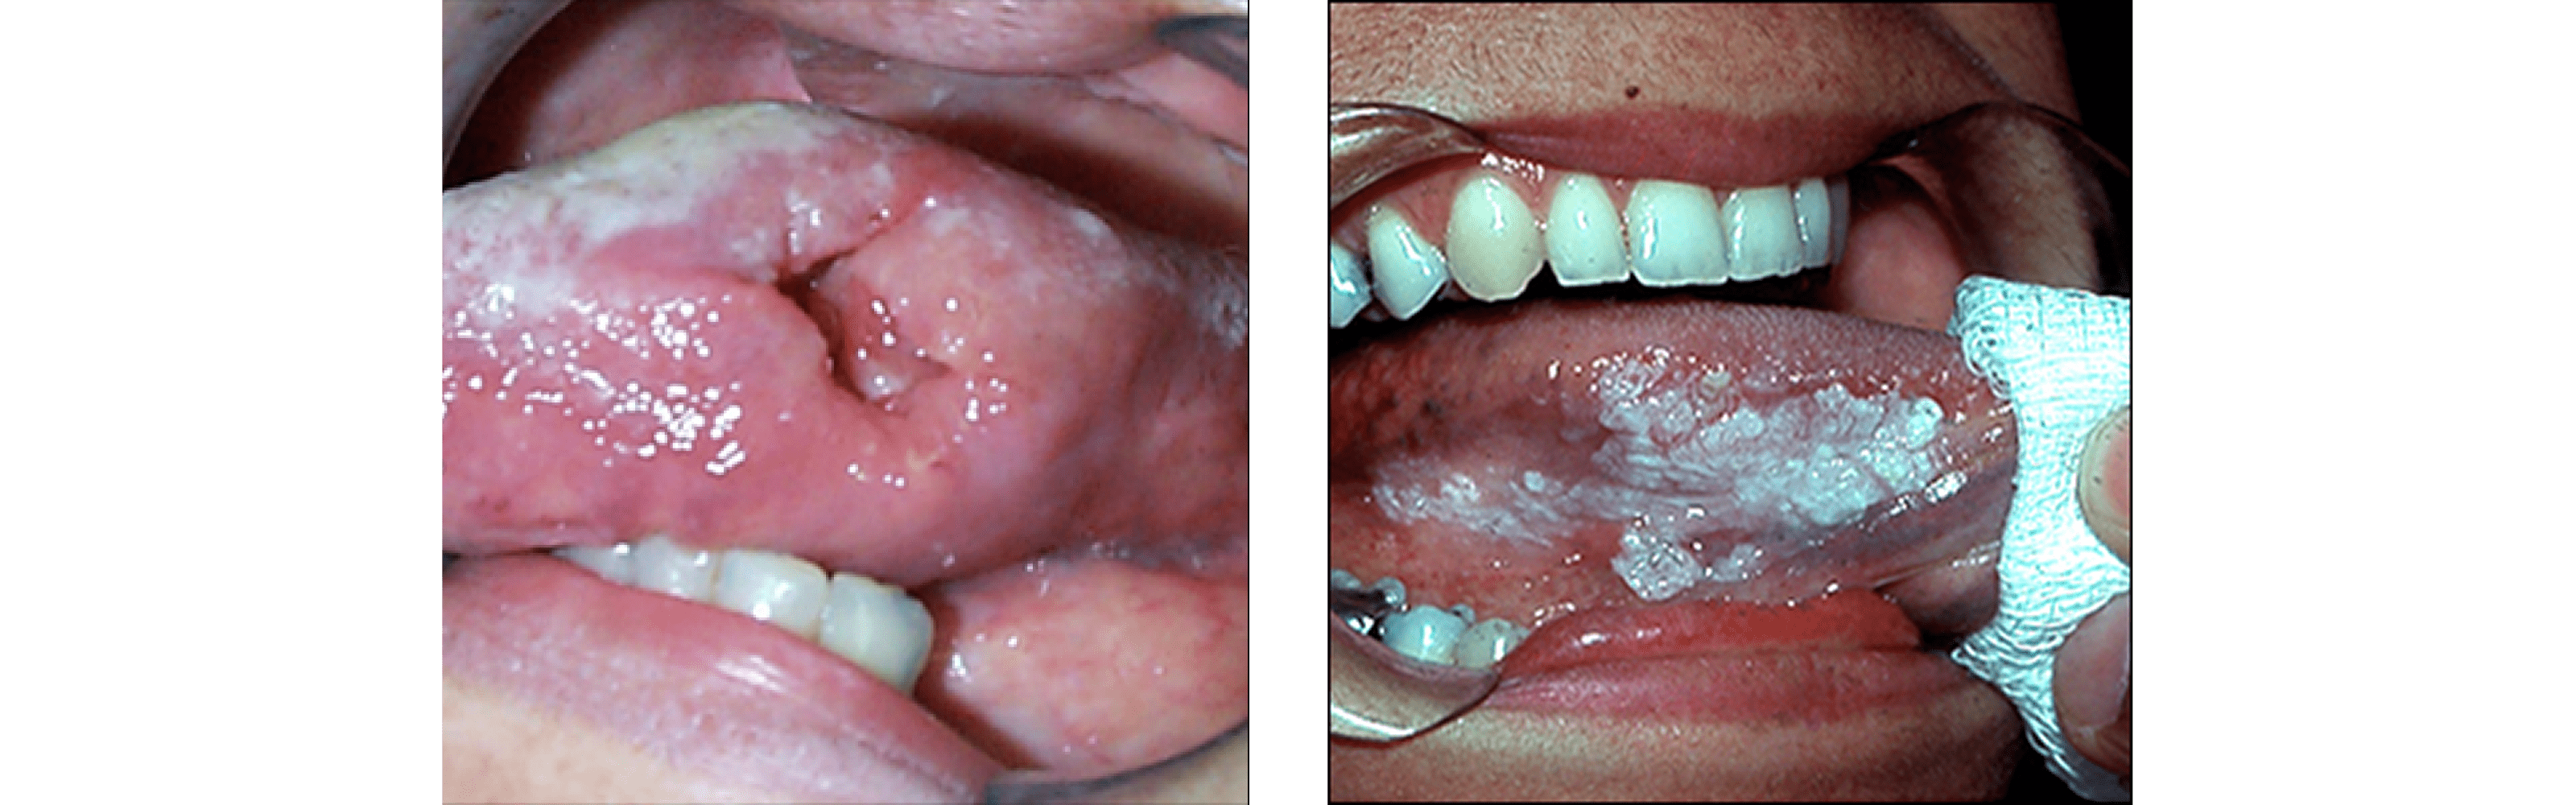

Oral Pathology

The inside of the mouth is normally lined with a special type of skin (mucosa) that is smooth and coral pink in color. Any alteration in this appearance could be a warning sign for a pathological process. The most serious of these is oral cancer. The following can be signs at the beginning of a pathologic process or cancerous growth:

• Reddish patches (erythroplakia) or whitish patches (leukoplakia) in the mouth

• A sore that fails to heal and bleeds easily

• A lump or thickening on the skin lining the inside of the mouth

• Difficulty in chewing or swallowing

• Expansion of the bone of the upper and/or lower jaw (may be indicative of a cyst or tumor)

These changes can be detected on the lips, cheeks, palate, gum tissue around the teeth, tongue, face and/or neck. Pain does not always occur with pathology, and curiously, is not often associated with oral cancer. However, any patient with facial and/or oral pain without an obvious cause or reason may also be at risk for oral cancer.

We would recommend performing oral cancer self-examination monthly and remember that your mouth is one of your body's most important warning systems. Do not ignore suspicious lumps or sores.

Pathologic changes in the mouth can occur in the form of benign and malignant lesions of the mucosa, the bone (cysts and tumors) and salivary glands. Manifestations of systemic diseases affect the mouth and can be one of the first signs to appear, therefore a key point to diagnose problems in other tissues. The treatment for oral lesions depends on the cause. Treatment for oral lesions may include non surgical options like antibiotics, antiviral medications, antiseptic mouthwash, anti-inflammatory and pain medications. Additional treatment may include surgery to remove an oral lesion.

A biopsy should be done for any suspicious premalignant or malignant lesion. A small piece of tissue is taken from the affected area and sent to the pathology lab. A diagnosis is obtained in 3-7 days. Then the oral and maxillofacial surgeon can perform the definitive surgery. Usually this is done in an office setting under intravenous sedation.  For the treatment of very aggressive benign lesions or malignant tumors patients need to be taken to the operating room and be treated under general anesthesia.

Surgery still remains as the main stay treatment for most of the oral lesions including oral cancer